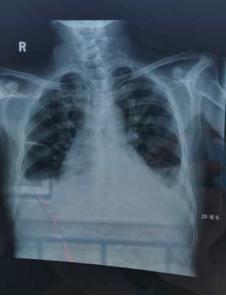

第二日老纪坐着轮椅再次来到我中心,果然状态比前一日更重,查体颜面及双下肢浮肿好转,但听诊双肺满布湿啰音,为什么透析清除了1公斤多的水分,心衰仍加重了呢?我们再次向张凌主任汇报老纪的病情,张主任经验丰富,考虑老纪是容量负荷太重,第一次透析清除了1公斤水属于杯水车薪,反而是下机回水的200ml由于在相对较短时间内回输到体内,竟成了加重老纪心衰的“最后一根稻草”。果然我们为老纪拍了X线胸片:心影增大,大量胸腔积液,保守估计还有3-4kg的水负荷。紧接着按照张主任指示,我们立即为老纪抬高床头、吸氧、上机先单纯超滤1小时脱水0.8kg(透析前查血电解质尚平稳),透析3个小时,总共脱水2.3kg,随着治疗时间的延长,老纪端坐呼吸症状逐渐减轻了,也开始起了困意,在护士的帮助下,摇低床头也可以平稳了睡着了。治疗结束后,老纪状态明显好转,家属紧绷的神经也放松了下来。这时张主任对我们提问:“为什么患者的体重一直在下降,但是水负荷以及心衰仍在加重?”的确,这是需要我们思考的问题,原来,心衰、水肿的患者,体循环负荷大,胃肠道淤血、水肿,导致患者本身食欲差,摄入少,另一方面,肠壁的水肿也减少了营养物质的吸收。而且处于慢性肾脏病终末期,老纪本身就存在贫血、低蛋白血症、营养不良等并发症,所以老纪近期下降的是瘦体重,但是水却仍在悄无声息的增加。针对老纪的情况,我们也为其制定了个体化的营养食谱,低盐、优质蛋白、足够能量摄入,辅助老纪安全度过诱导透析阶段。“太感谢你们了,如此全面的治疗,每一步都是从我们的患者的角度着想,感谢!感恩!……”老纪及家属的话语更加增强了我们的职业责任感与使命感!